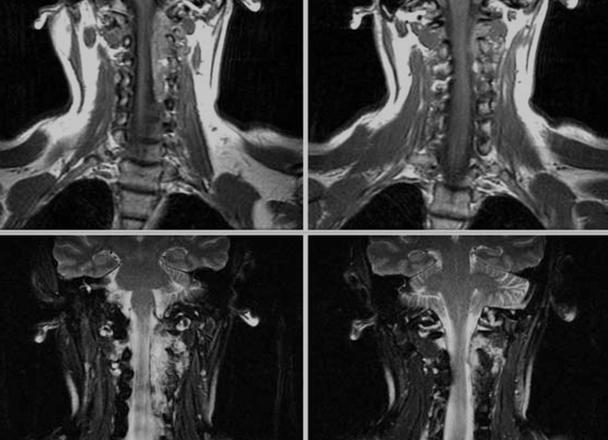

МРТ мягких тканей грудной клетки – это неинвазивный инструментальный метод диагностики, обеспечивающий детальную визуализацию мягких структур данного отдела. МРТ диагностика мягких тканей грудной клетки подразумевает исследование рыхлой межмышечной и синовиальной ткани, лимфатических узлов, нервов, кожно-жировой прослойки, нервов, кровеносных сосудов, поперечно-полосатых мышц и соединительно-тканных прослоек.

Уникальность МРТ при исследовании мягких тканей грудной клетки заключается в том, что рентген и даже компьютерная томография не предоставляет столь обширных данных, ввиду чего информативность альтернативных методик снижена. Магнитно-резонансная томография превосходит остальные виды процедур и в плане безопасности. Скрининг с применением магнитных полей позволяет пациенту без боли и нарушения целостности тканей уточнить свой диагноз, не получив при этом ни малейшей доли радиации. МРТ мягких тканей грудной клетки с контрастным веществом поможет выявить начальный этап аномальных изменений, что особенно актуально при подозрении на развитие злокачественного образования и распространение метастазов.

Оптимальная визуализация мягких тканей достигается на аппаратах с высокой мощностью магнитного поля. Дополнительно для уточнения локализации процесса задействуются градиентные катушки, обеспечивающие селективное возбуждение протонов. В процессе исследования производится несколько срезов, которые после компьютерной обработки дают детальную информацию о структурных особенностях исследуемой зоны.

Магниторезонансная томография обладает высокой чувствительностью в отношении даже мелких патологических процессов. Это неинвазивная методика, которая в ряде случаев становится даже более результативной, чем КТ. В основном это касается исследования мягких тканей, богатых жидкостью. Среди преимуществ МРТ стоит отметить отсутствие лучевой нагрузки, а также возможность оценки функции органа (скорость кровотока, степень диффузии).

С помощью МРТ определяют размеры, локализацию и распространенность опухолевого процесса, оценивается состояние сердца, кровоток в нем, функция клапанного аппарата. Это имеет значение при патологии, осложнившейся недостаточностью кровообращения или кардитом. Выбор в пользу такой томографии делают при невозможности получить необходимую информацию другими методами.